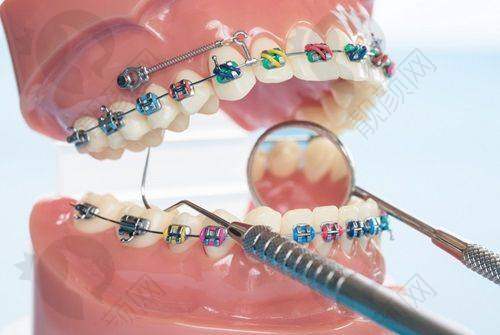

宁波鄞州德中口腔门诊部 - 牙齿正畸 - 传统金属矫正8000 - 15000元

患者评价二:之前牙齿不齐,一直想矫正。朋友推荐了宁波鄞州德中口腔门诊部,就过来试试。医生根据我的牙齿情况制定了个性化的正畸方案,戴上牙套后也没有特别不舒服。每次复诊,医生都会耐心调整。现在牙齿越来越整齐了,对治疗成效特别满意,也特别感谢这里的医生和工作人员。